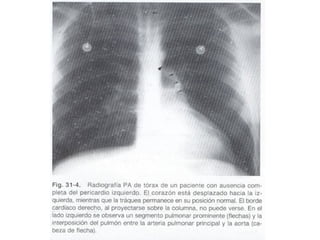

LA AUSENCIA CONGÉNITA DEL PERICARDIO.